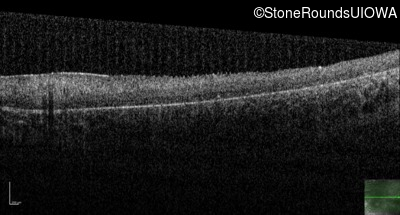

Optical Coherence Tomography - Right - 20/200 sc

Exemplar / OCT Stack